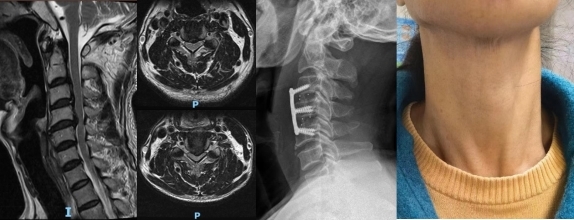

颈椎病的外科治疗处于国内领先水平,每年完成各类颈椎手术逾600台,平均住院日小于4天,是中国医师协会脊柱显微学组副组长单位。国内最早开展显微镜下颈椎前后路手术,颈椎前路ACDF手术已然发展为日间手术。国内率先开展内镜辅助下经口咽寰枢椎复位,颈椎极重度畸形矫形手术、颈椎双通道内镜下椎管减压及椎间盘切除术为国内、国际领先水平。依托术前三维CT模拟手术规划、AI辅助颈椎病诊断及预后分析平台,将颈椎病的诊疗推向微创化、精准化的新时代。科室是华南地区显微镜技术培训基地,每年举办相关专题的国家级和省级继续教育培训班,常年招收相关临床技能培训学员。

颈椎病微创小切口